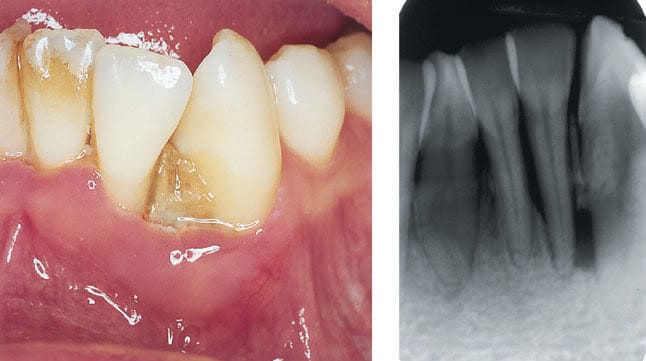

LÂM SÀNG VÀ XQUANG: (biểu hiện bệnh)

Mảng bám trên và dưới lợi,

Viêm lợi (sưng nề, màu đỏ hay đỏ rực, một  số bệnh nhân thay đổi màu sắc lợi và sưng lợi không rõ, chỉ phát hiện được viêm khi thăm khám thấy chảy máu) . Một số  trường hợp khám lợi khó phát hiện thấy dấu hiệu viêm lợi vì do quá trình  viêm mãn tính kéo dài làm lợi xơ dày lên che tổ chức lợi viêm bên dưới.(Theo như giáo trình y khoa bệnh vùng quanh răng của Thạc sĩ Ngô Quý Vũ )

– Tiết nhiều dịch túi lợi.

Túi quanh răng, mất bám dính và tiêu xương ổ răng,

Lung lay răng là hậu quả của mất bám  dính và tiêu xương ổ răng.

Xquang: tiêu xương ổ răng, dấu hiệu xquang giống với VQR khó kiểm soát (aggressive)

Tiêu xương có thể là tiêu xương chéo (vertical) tạo túi trong xương, hay tiêu xương ngang (horizontal) với túi lợi trên xương.

Hình ảnh tiêu xương ổ răng vùng răng cửa